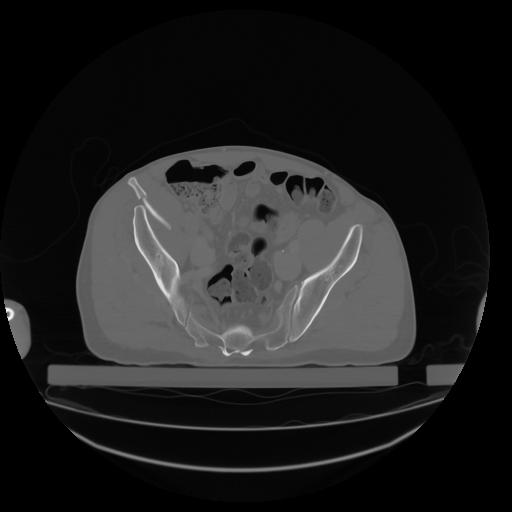

27 CUERPO,CE,Axial,3.0,CUERPO,,